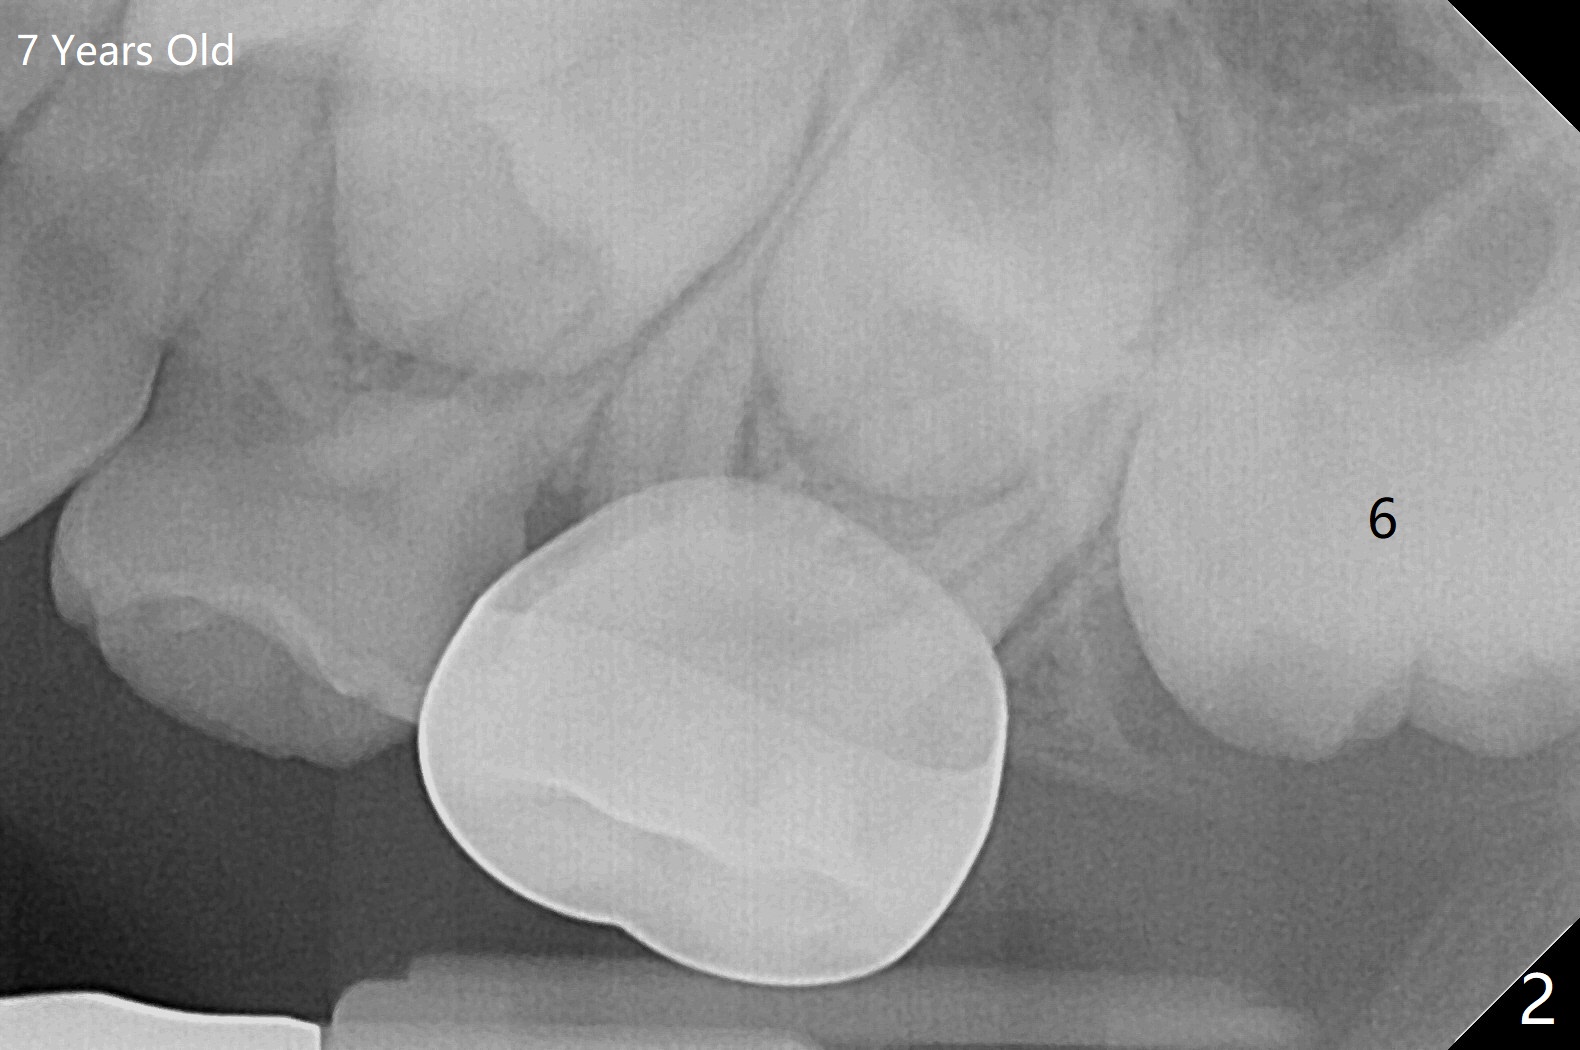

The upper left 1st permanent molar of a female remains unerupted between the age of 6 and 8 years old (Fig.1-4). The distal root of E is resorbed (Fig.3), which may be a reason of blockage. It appears that the upper left molars are underdeveloped, including 7. Or UL6 is congenitally missing? What is the treatment plan? Wait or surgery?

I have seen this before where a 6 looks like a 7! It behaves like a ‘9-year

molar’ in terms of root development and eruption! It is a variant.